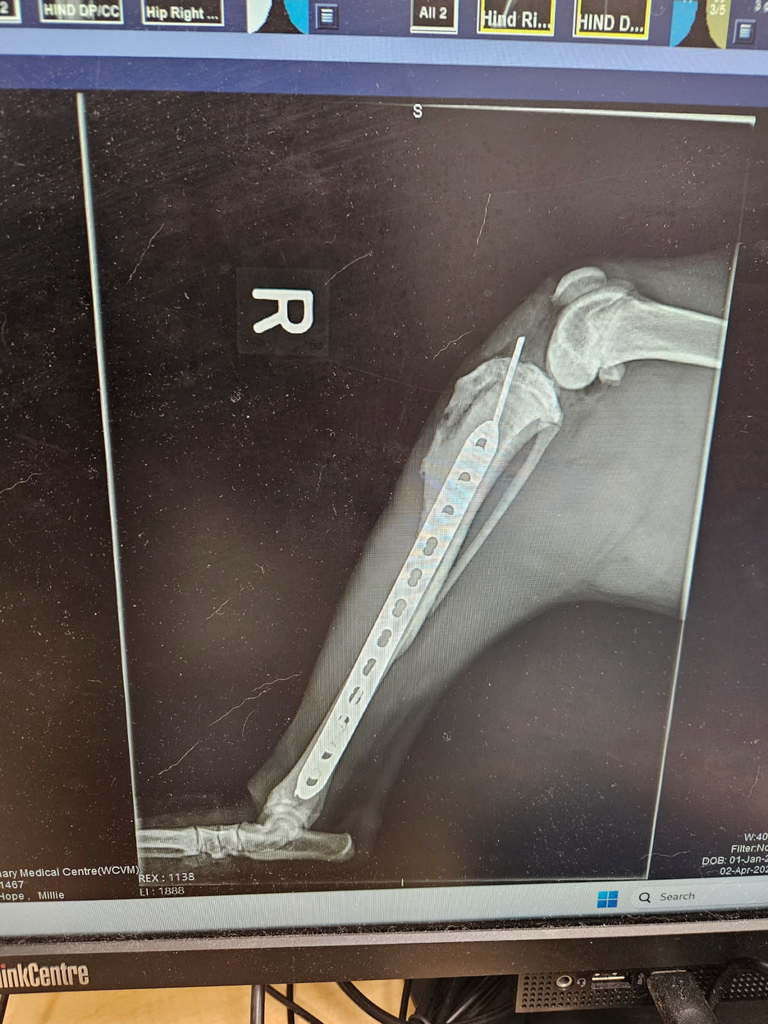

On a Wednesday Milly found herself at the mercy of a vehicle. It was hoped that she would recover without medical intervention, but when Friday arrived the decision was made to get Milly to the clinic, she wasn’t using her right leg and was choosing not to move around much at all. Thankfully our friends at Canine Action Project got her to Park Range Veterinary Services where it was discovered that her hind right tibia was fractured. She was stabilized while we looked for a foster and brought to the WCVM Small Animal Clinic so she could be observed and monitored until her surgery. The team working with her reported that she was a very good patient, sweet with everyone, eating her meals, and eager to go for walks as her pain was controlled. She was also taken for further x-rays and a CT Scan that confirmed she did have some damage around her lungs and a fracture at the sacroiliac joint that was causing luxation. On Wednesday, April 2nd, Milly underwent a 6 hour surgery to repair both fractures. It was reported that she is a young, healthy dog, so her body was already creating new calcification near the tibial fracture that made it difficult for a ‘perfect’ repair, but it was a good repair all the same. Milly is not resting and recuperating in her foster home, it is expected that she will start some rehabilitation work in a week or two to help her through the healing process. She will need 6-8 weeks to heal before she can be adopted.

On an ordinary Wednesday, Millie’s life was forever changed when she was struck by a vehicle and left hurting, frightened, and unsure if help would come. By Friday, her pain could no longer be ignored—she couldn’t use her leg, barely moved, and yet still greeted everyone with quiet sweetness as scans revealed multiple fractures and internal injuries no one could see from the outside. Millie endured a six-hour surgery and weeks of strict recovery, bravely choosing patience over play while her body slowly learned how to heal again. Because of lifesaving medical care, dedicated fosters, and supporters who believed she was worth fighting for, Millie has made it through—and today she is healed. But Millie knew she was home all along when her foster made the decision to keep her.